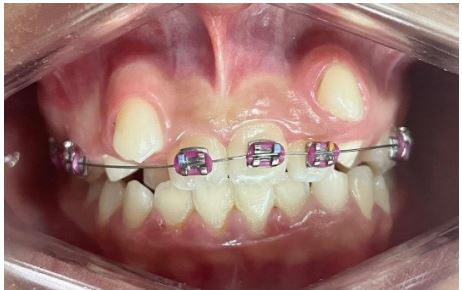

After analysis of the radiographic exams, a fixed mettalic Roth ligh from Morelli with Niti 12 wire was installed, as shown in (Figure 4). Subsequently, the orthodontic appliance was maintained with Niti 12 wire in the upper arch plus cementation of orthodontic bands in elements 16 and 26 (Figure 5), extraction of the two upper primary canines and lower left primary canine that were in prolonged retention and subsequent maintenance (Figure 6) presenting in A the third maintenance and in B was performed installation of the appliance in the lower arch plus maintenance with Niti wire 16 in the upper and lower arches, conjugated ligature from element 32 to 46, Morelli medium elastic chain from tooth 33 to 32 and bonding of teeth 13 and 23, and in C the fifth consultation with evolution of the lower Niti wire 18 with conjugated ligature of element 32 to 44, elastic chain on tooth 33 to 32, steel wire 16 in the upper arch, open spring between teeth 11 and 14 and between 22 and 24 and in D end E the subsequent maintenance until the present moment (Figure 7)

Figure 7: (a) Third visit, maintenance of the Niti 14 wire; (b) Fourth consultation, installation of the apparatus in the lower arch; (c) fifth consultation; (d) sixth consultation; (e) seventh maintenance; (f) Eighth maintenance and the last maintenances until the presente moment in G. (Source: The Authors, 2023).